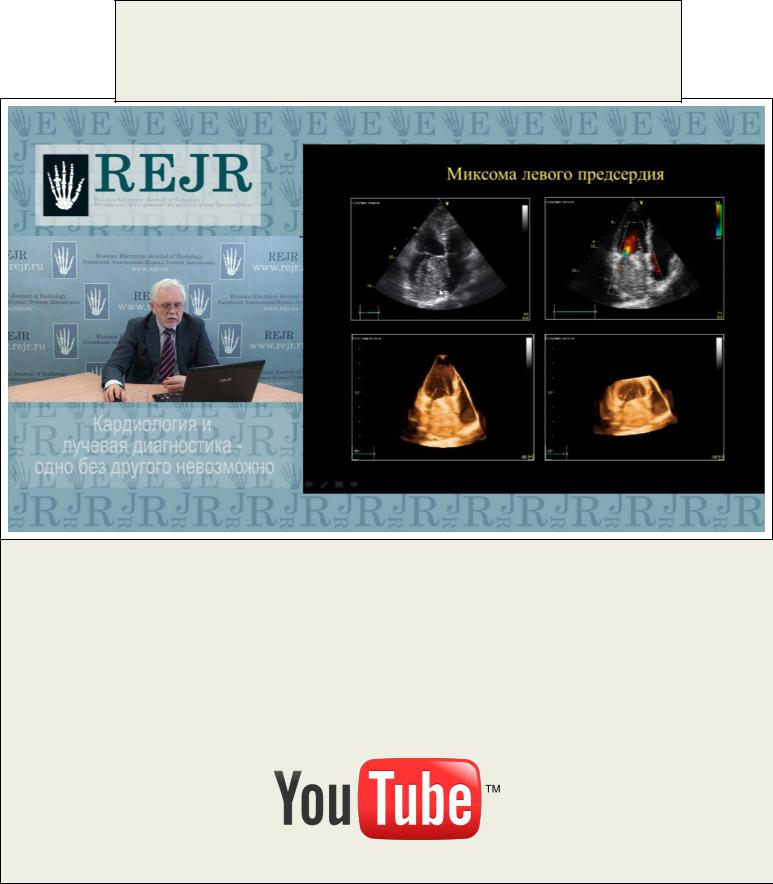

МАСТЕР-КЛАСС.

КАРДИОЛОГИЯ И ЛУЧЕВАЯ ДИАГНОСТИКА - ОДНО БЕЗ ДРУГОГО НЕВОЗМОЖНО

Седов В.П.

Современная кардиология немыслима без применения методов лучевой диагностики. Ультразвуковая диагностика давно зарекомендовала себя как один из главных методов выбора при проведении исследования пациенту с сердечной

патологией. Какие новые возможности ЭХО-КГ появляются в арсенале врача лучевой диагностики? Как результаты ЭХО-КГ-исследования дополняются другими методами лучевой диагностики? Сегодняшний мастер-класс даст ответы на эти и другие вопросы

Для просмотра мастер-класса перейдите на сайт: http://rejr.ru/devyatyi_nomer/master-class-Sedov.html

Мастер-класс. КАРДИОЛОГИЯ И ЛУЧЕВАЯ ДИАГНОСТИКА - ОДНО БЕЗ ДРУГОГО НЕВОЗМОЖНО